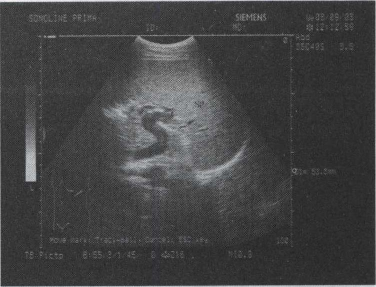

47.某患者脾脏声像图表现如图,诊断为()